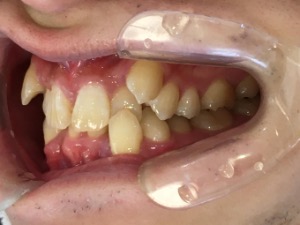

before

after

患者さんの年齢 20代 女性 症状 ガタガタを治したい 治療内容 マウスピース矯正治療 費用 90万(税抜) 治療期間・回数 治療期間2年、通院回数10回 メリット 笑顔が綺麗 デメリット・リスク 期間がかかることがある - マウスピース矯正